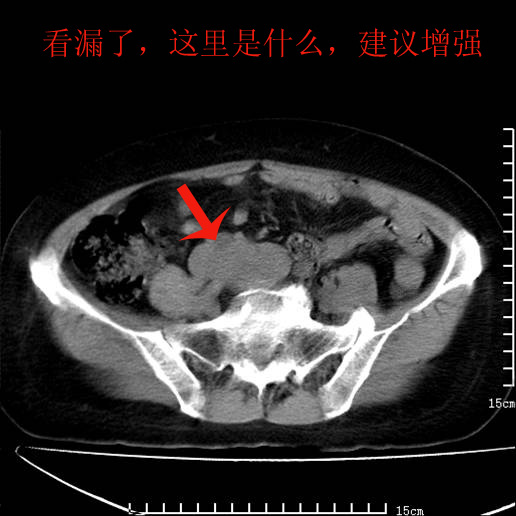

以下是引用pujunzhi在2008-5-30 15:31:00的发言:[br]异位肾—盆腔肾。当看到肾窝无肾脏时,要想到孤立肾和异位肾,异位肾最常见是盆腔肾,偶见胸腔,易误认为肺占位,只要想到就不会漏诊。建议增强扫描。